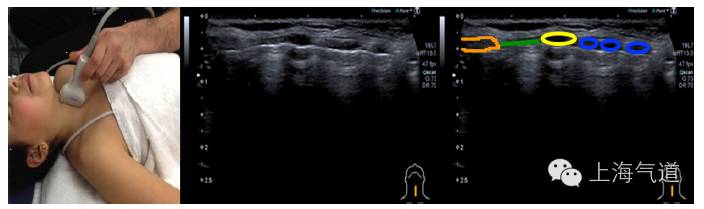

图6探头置于颈部取纵切面,橙色标记为甲状软骨,绿色为环甲膜,黄色为环状软骨,蓝色为气管环,气管内空气向下投射成连续的亮线,因而妨碍了深部结构的成像